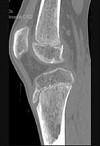

- 单项选择题男,46岁, 膝关节疼痛,结合图像, 最可能的诊断是 ( )

A、骨质硬化

B、骨质疏松

C、骨质软化

D、骨髓瘤

E、转移瘤